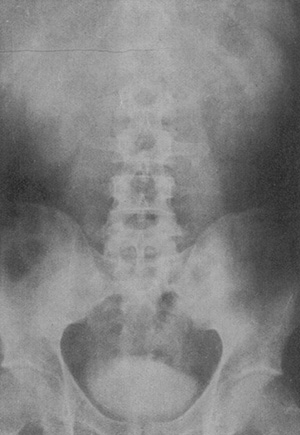

図1. ヨウ化ナトリウムによる経静脈性排泄性尿路造影.膀胱の描出は良いが,腎の造影は淡く,尿管は見えていない.

【要旨】従来腎盂造影に使われていた,組織障害性の強い銀コロイド造影剤に替わる造影剤として,ヨウ化ナトリウム(NaI)の経静脈性,経口投与を試みた(図1).それぞれについて造影剤の濃度,撮影のタイミングを詳細に検討して至適条件を求めた.経静脈性投与では,ヨウ化ナトリウム10%溶液を5~20g静注,0.5~3時間後に撮影,経口投与では3gを1時間毎に3回投与,1~2時間後に撮影すると良い.造影により,腎の陰影はわずかに濃度が上昇し,腎盂はさまざまな程度に造影され,尿管は多くの例で追跡できた.膀胱は全例において明瞭に描出された.

【解説】著者のOsborneは皮膚科医で,梅毒の専門医であった.当時,梅毒の治療法としてヨウ化ナトリウム(NaI)の大量投与が行なわれており,この患者にX線撮影を行なうことにより,その排泄性尿路造影剤としての応用を検討した論文である.膀胱は全例において明瞭に描出されたもの,腎盂,尿管は確実とはいえず,腎実質の造影効果はごく淡いものにとどまった.従来の逆行性腎盂造影に比較すればまだ不十分とはいえ,カテーテルを挿入せずに非侵襲的に尿路造影が得られたことは画期的なことであった.